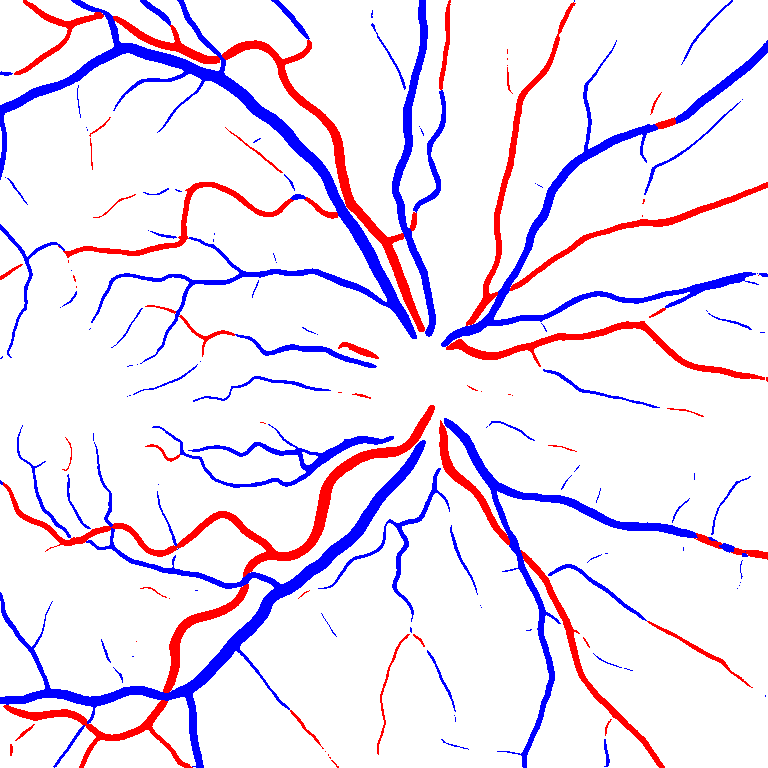

Table V presents quantitative performance benchmarks of SegRAVIR and other competing approaches for retinal artery and vein classification on the RITE dataset [11]. SegRAVIR outperforms previous state-of-the-art approaches in terms of accuracy, sensitivity, and specificity. Fig. 5 provides a qualitative comparison between segmentation outputs of SegRAVIR and the method of Hemelings et al. [40] on the RITE test set.